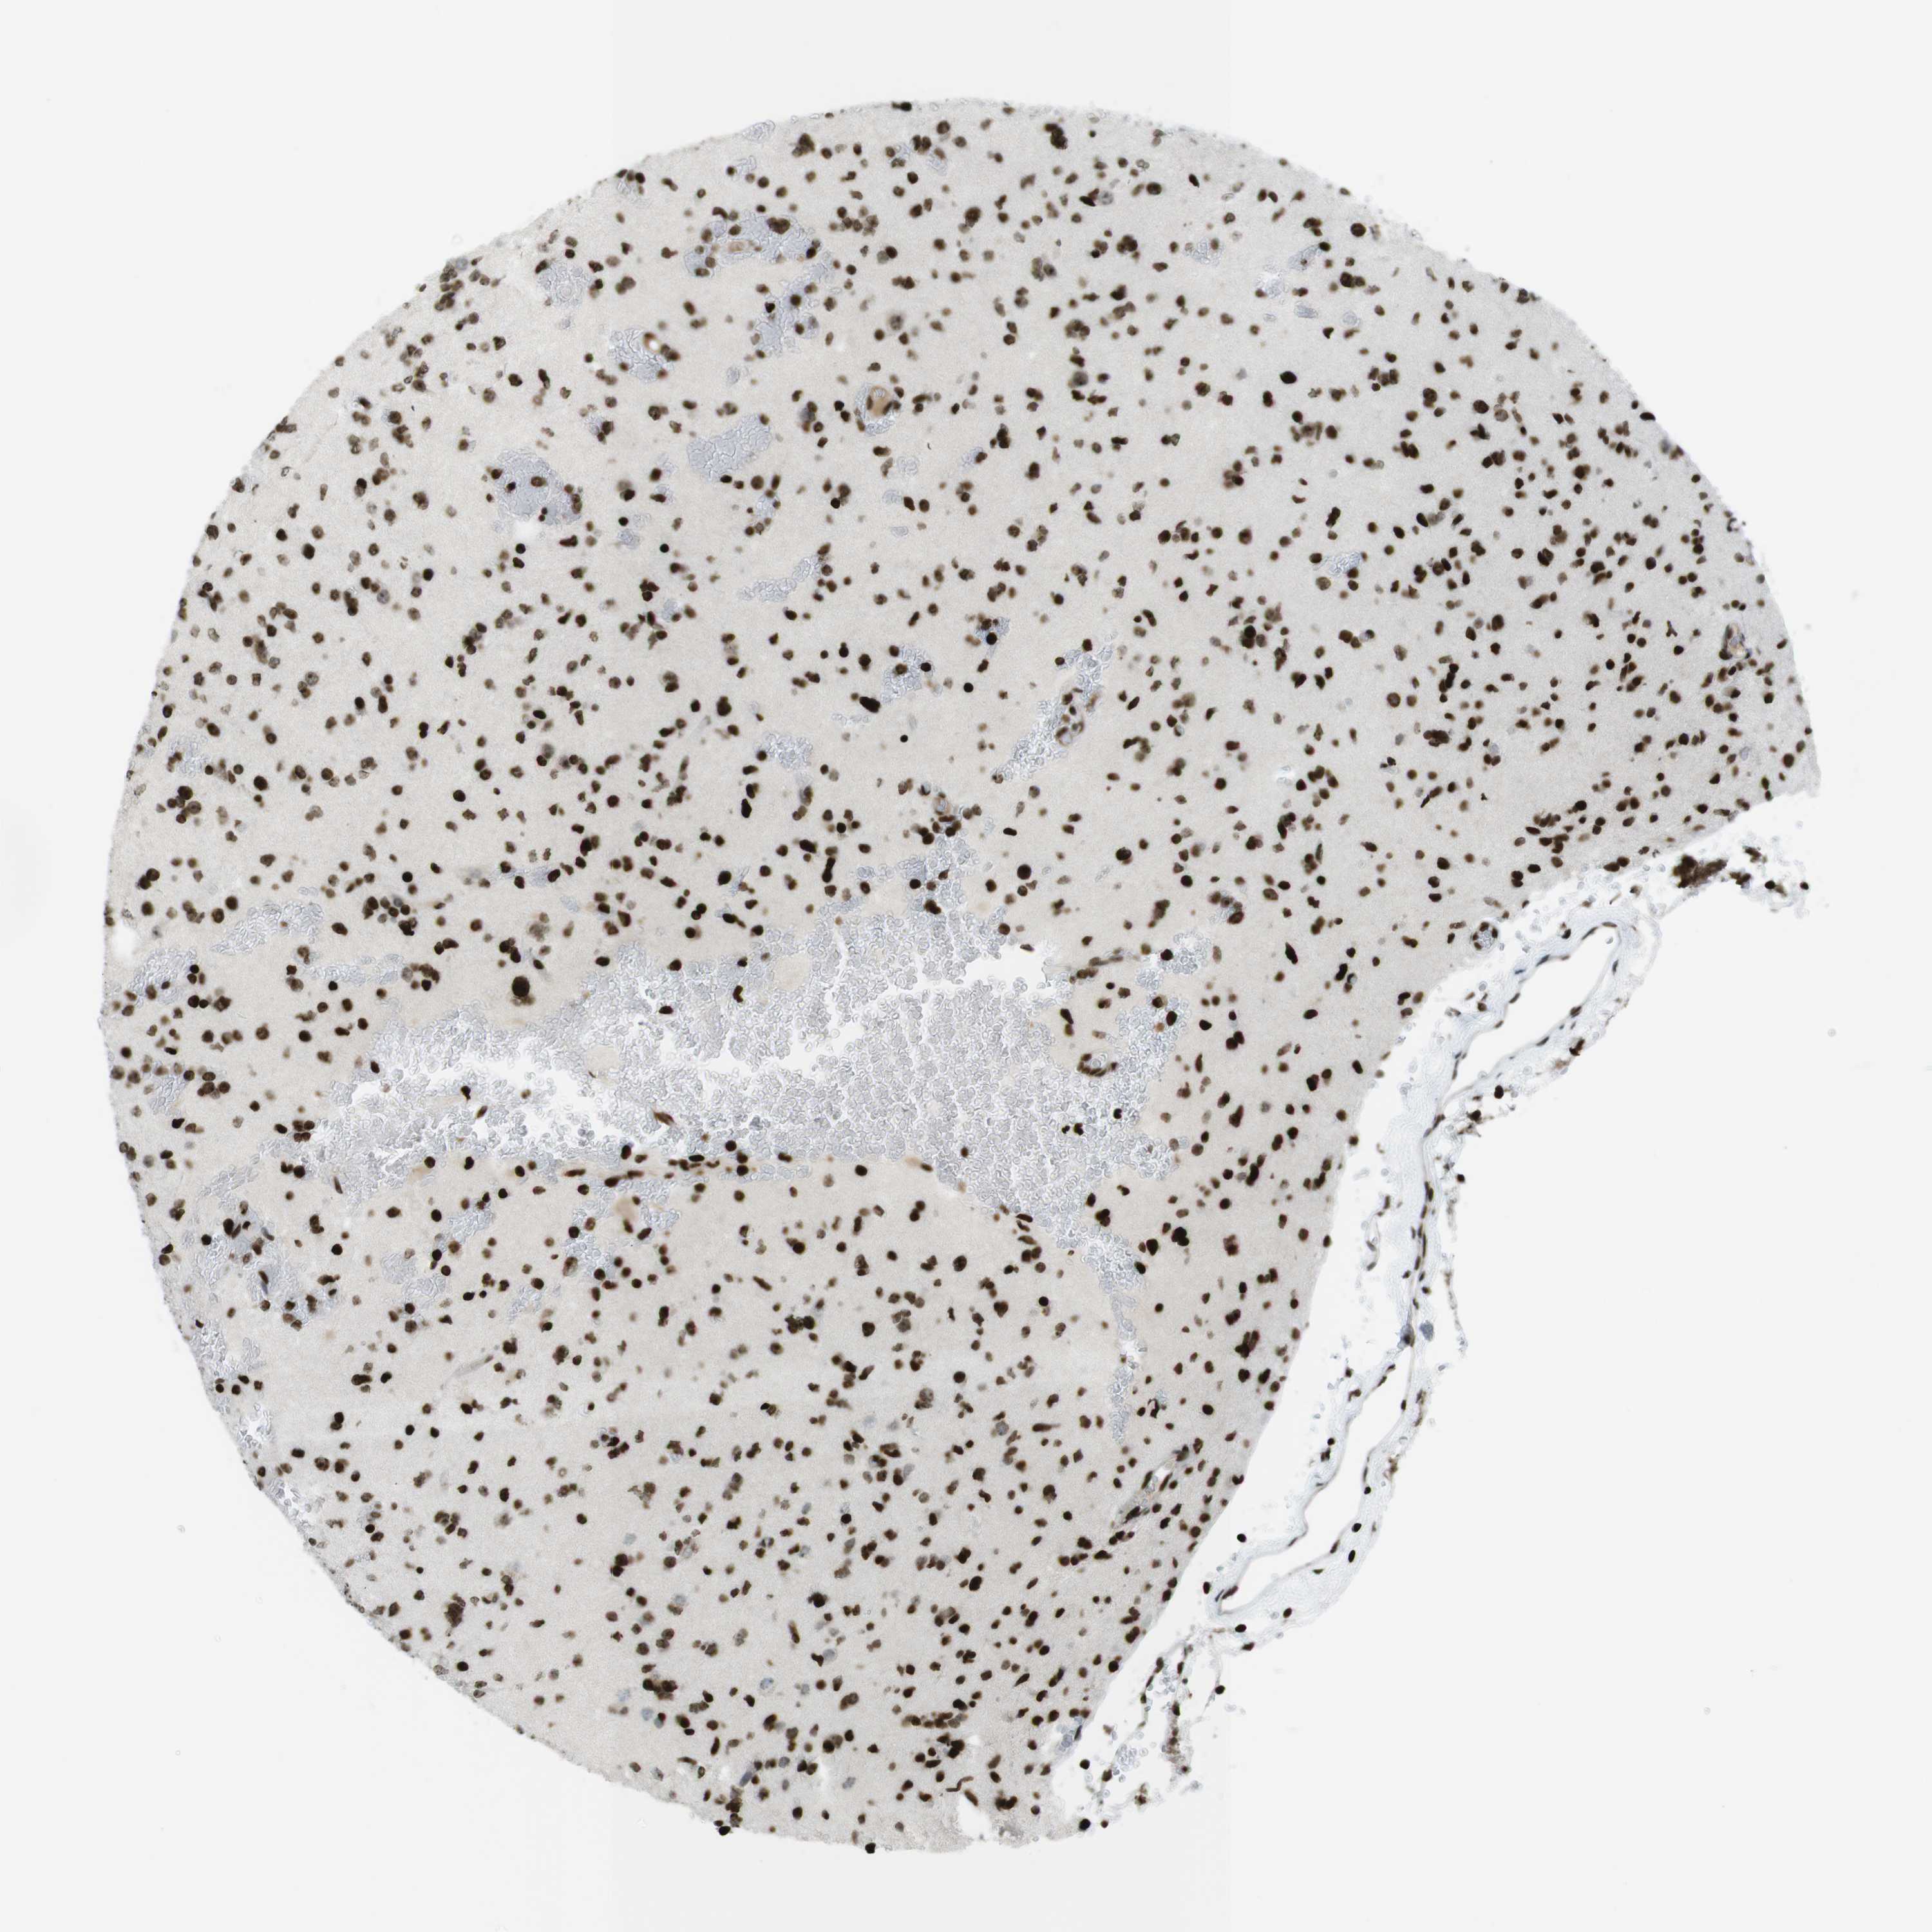

GLIOMA - Protein expressioni

A mouse-over function shows sample information and annotation data. Click on an image to view it in a full screen mode. Samples can be filtered based on level of antibody staining by selecting one or several of the following categories: high, medium, low and not detected. The assay and annotation is described here.

Note that samples used for immunohistochemistry by the Human Protein Atlas do not correspond to samples in the TCGA dataset.

Antibody stainingi

Antibody staining in the annotated cell types in the current human tissue is reported as not detected, low, medium, or high, based on conventional immunohistochemistry profiling in selected tissues. This score is based on the combination of the staining intensity and fraction of stained cells.

Each image is clickable and will lead to virtual microscopy that enables deeper exploration of all samples and also displays staining intensity scores, fraction scores and subcellular localization as well as patient and tissue information for each sample.

Antibody HPA041189

Antibody CAB012242

Staining

High

Medium

Low

Not detected

Intensity

Strong

Moderate

Weak

Negative

Quantity

>75%

75%-25%

<25%

None

Location

Nuclear

Cytoplasmic/membranous

Cytoplasmic/membranous,nuclear

Glioma, malignant, High grade

Glioma, malignant, Low grade